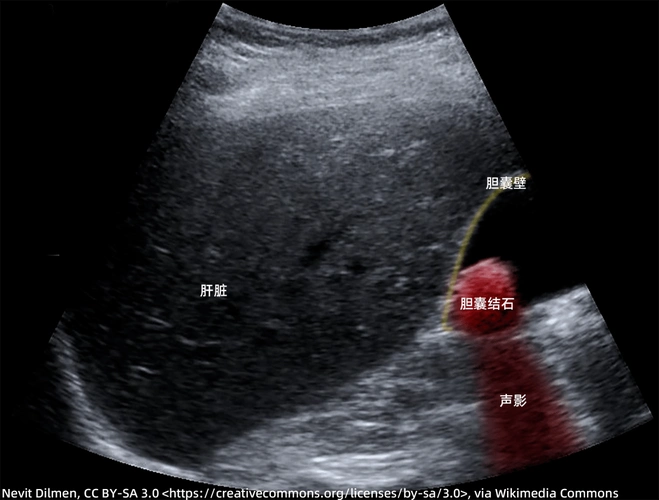

每日技能影像学超声之胆囊结石